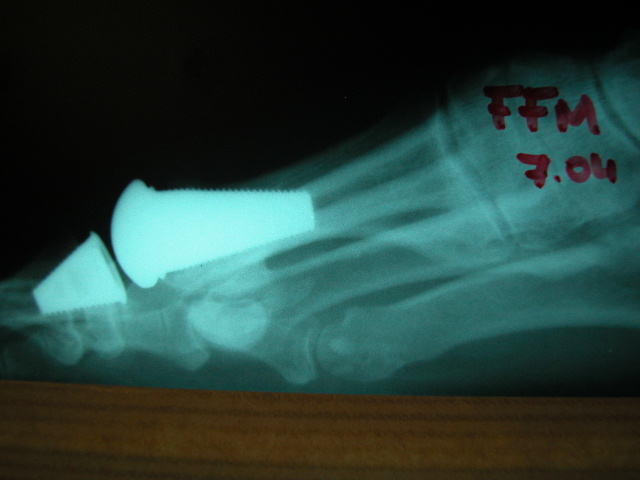

ACT Prótesis de hallux en artrosis.

ACT Prótesis de hallux. Perfil.